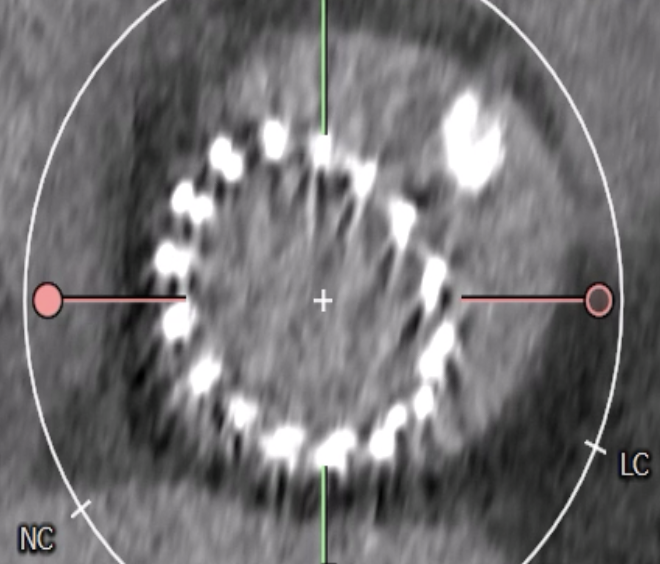

Multidetector CT was performed to assess the risk of coronary obstruction in the context of redo TAVI. The assessment focused on the spatial relationship between the neoskirt plane of the degenerated CoreValve and the coronary risk plane. The perimeter-derived annular diameter of failed CoreValve was 21.3 mm, guiding the selection of a 26-mm Evolut PRO valve. The narrowest valve-to-coronary distances measured 4.3 mm for the left main and 2.4 mm for the RCA.

Relevant Catheterization Findings